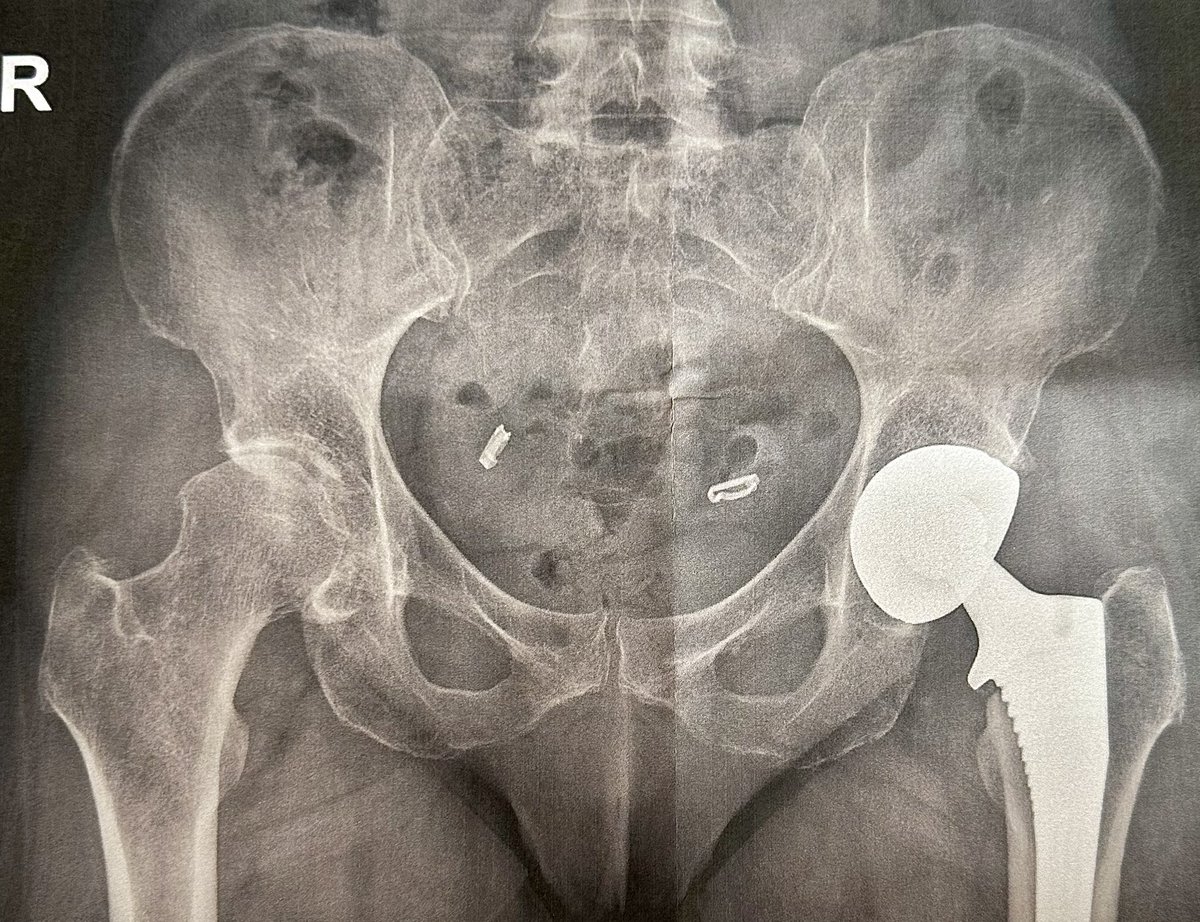

Vid 2. So the july 11th was surgery. This july 13 postop. Swelling was starting. Got tad uncomfortable. Elevate and ice. Hydrate best you can. My appetite was gone! #hipreplacements #postoperation #recovery #surgery #Healing #myjourney #sheilableck #athletes